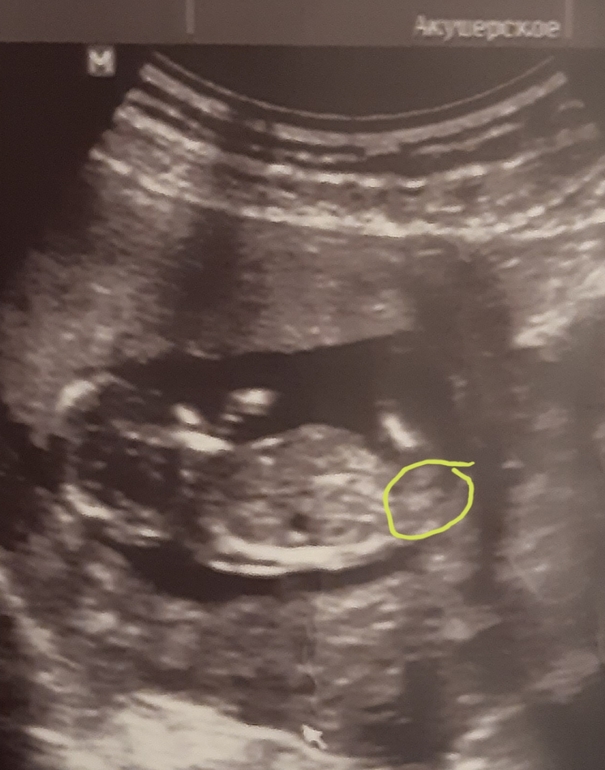

Особенности УЗИ при определении пола ребенка

Раздел: Идеи и советы